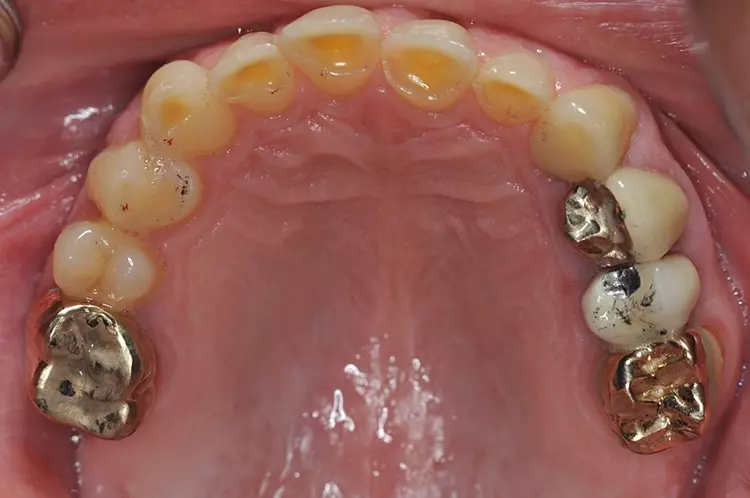

Die präzise Passung wird bei metallfreien Restaurationen heute nicht mehr unbedingt zum primären Ausbildungsziel erhoben, da das Vertrauen in das Kleben von Restaurationen selbst am Dentin groß ist. Die klassischen und ehemals weitverbreiteten Goldrestaurationen sind gegossene Voll- und Teilkronen sowie Inlays und Overlays im Seitenzahnbereich. Die dazu verwendeten Gold-Platin-Legierungen sind seit Jahrzehnten bewährt und gut zu verarbeiten.

Ihre Biokompatibilität ist erwiesen und sie gehören zu den minimalinvasiven Restaurationsformen, da sie unverblendet sind. Ihr großer Vorteil liegt darin, dass sie sich funktionell perfekt in die Mundhöhle einpassen.

Sie erlauben eine gewisse Abnutzung durch Abrasion und Attrition, sind aber wiederum sehr langzeitstabil, sodass es Studien zu Restaurationen mit erfolgreichen Nutzungsdauern über dreißig Jahre gibt. Wenn man also nicht die Wünsche nach zahnfarbenen Restaurationen als primäres Behandlungsziel sieht, sind hochgoldhaltige Restaurationen im Seitenzahnbereich unter funktionellen Gesichtspunkten die Versorgung der ersten Wahl und durch die jahrzehntelangen Erfahrungen auch im übertragenen Sinne der Goldstandard.

Es ist sicher sinnvoll, mit dem Patienten zu überlegen, ob sich nicht die primär größere Investitionssumme in Gold langfristig durch eine längere Nutzungsdauer und problemlosere Nutzungsphase auszahlt. Ein guter Kompromiss könnte bei der Sanierung in allen 4 Quadranten die Goldkaufläche im Oberkiefer und die glaskeramische Kaufläche aus ästhetischen Gründen im Unterkiefer sein. Letztere wird vom Betrachter eher wahrgenommen als Restaurationen im Oberkiefer.